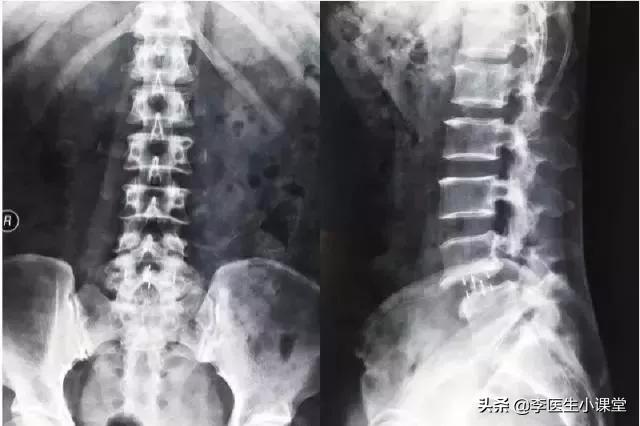

但是腰间盘突出是无法单从病症判断的,必须有病症与影像学检查结果才能确认。随后医生叫黄先生去做了腰椎X线平片和CT检查。

黄先生的腰椎X线平片可以看到,他的腰椎确实是有一定程度的突出。

检查所见: 腰椎生理曲度存在,部分椎体缘骨质增生、变尖、椎体未见明确骨质破坏征象,腰3/4、腰4/5椎尖盘突出,硬膜囊受压,对应椎管及椎间孔通常,腰5/骶1椎尖盘形态大致正常。所示各小关节关系未见明确异常改变。

主诉: 腰部疼痛、下肢麻木。

现有病史: 腰痛间歇性发作长达十余年,下肢麻木无力。